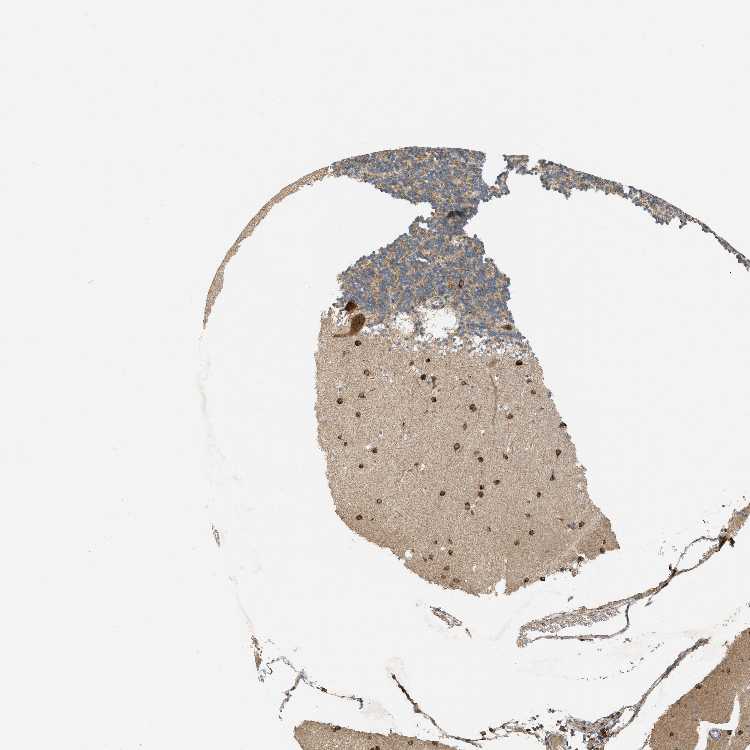

CEREBELLUM - Antibody stainingi

Antibody staining in the annotated cell types in the current human tissue is reported as not detected, low, medium, or high, based on conventional immunohistochemistry profiling in selected tissues. This score is based on the combination of the staining intensity and fraction of stained cells.

Each image is clickable and will lead to virtual microscopy that enables deeper exploration of all samples and also displays staining intensity scores, fraction scores and subcellular localization as well as patient and tissue information for each sample.

Antibody HPA017976

Purkinje cells High

Cells in granular layer Medium

Cells in molecular layer High